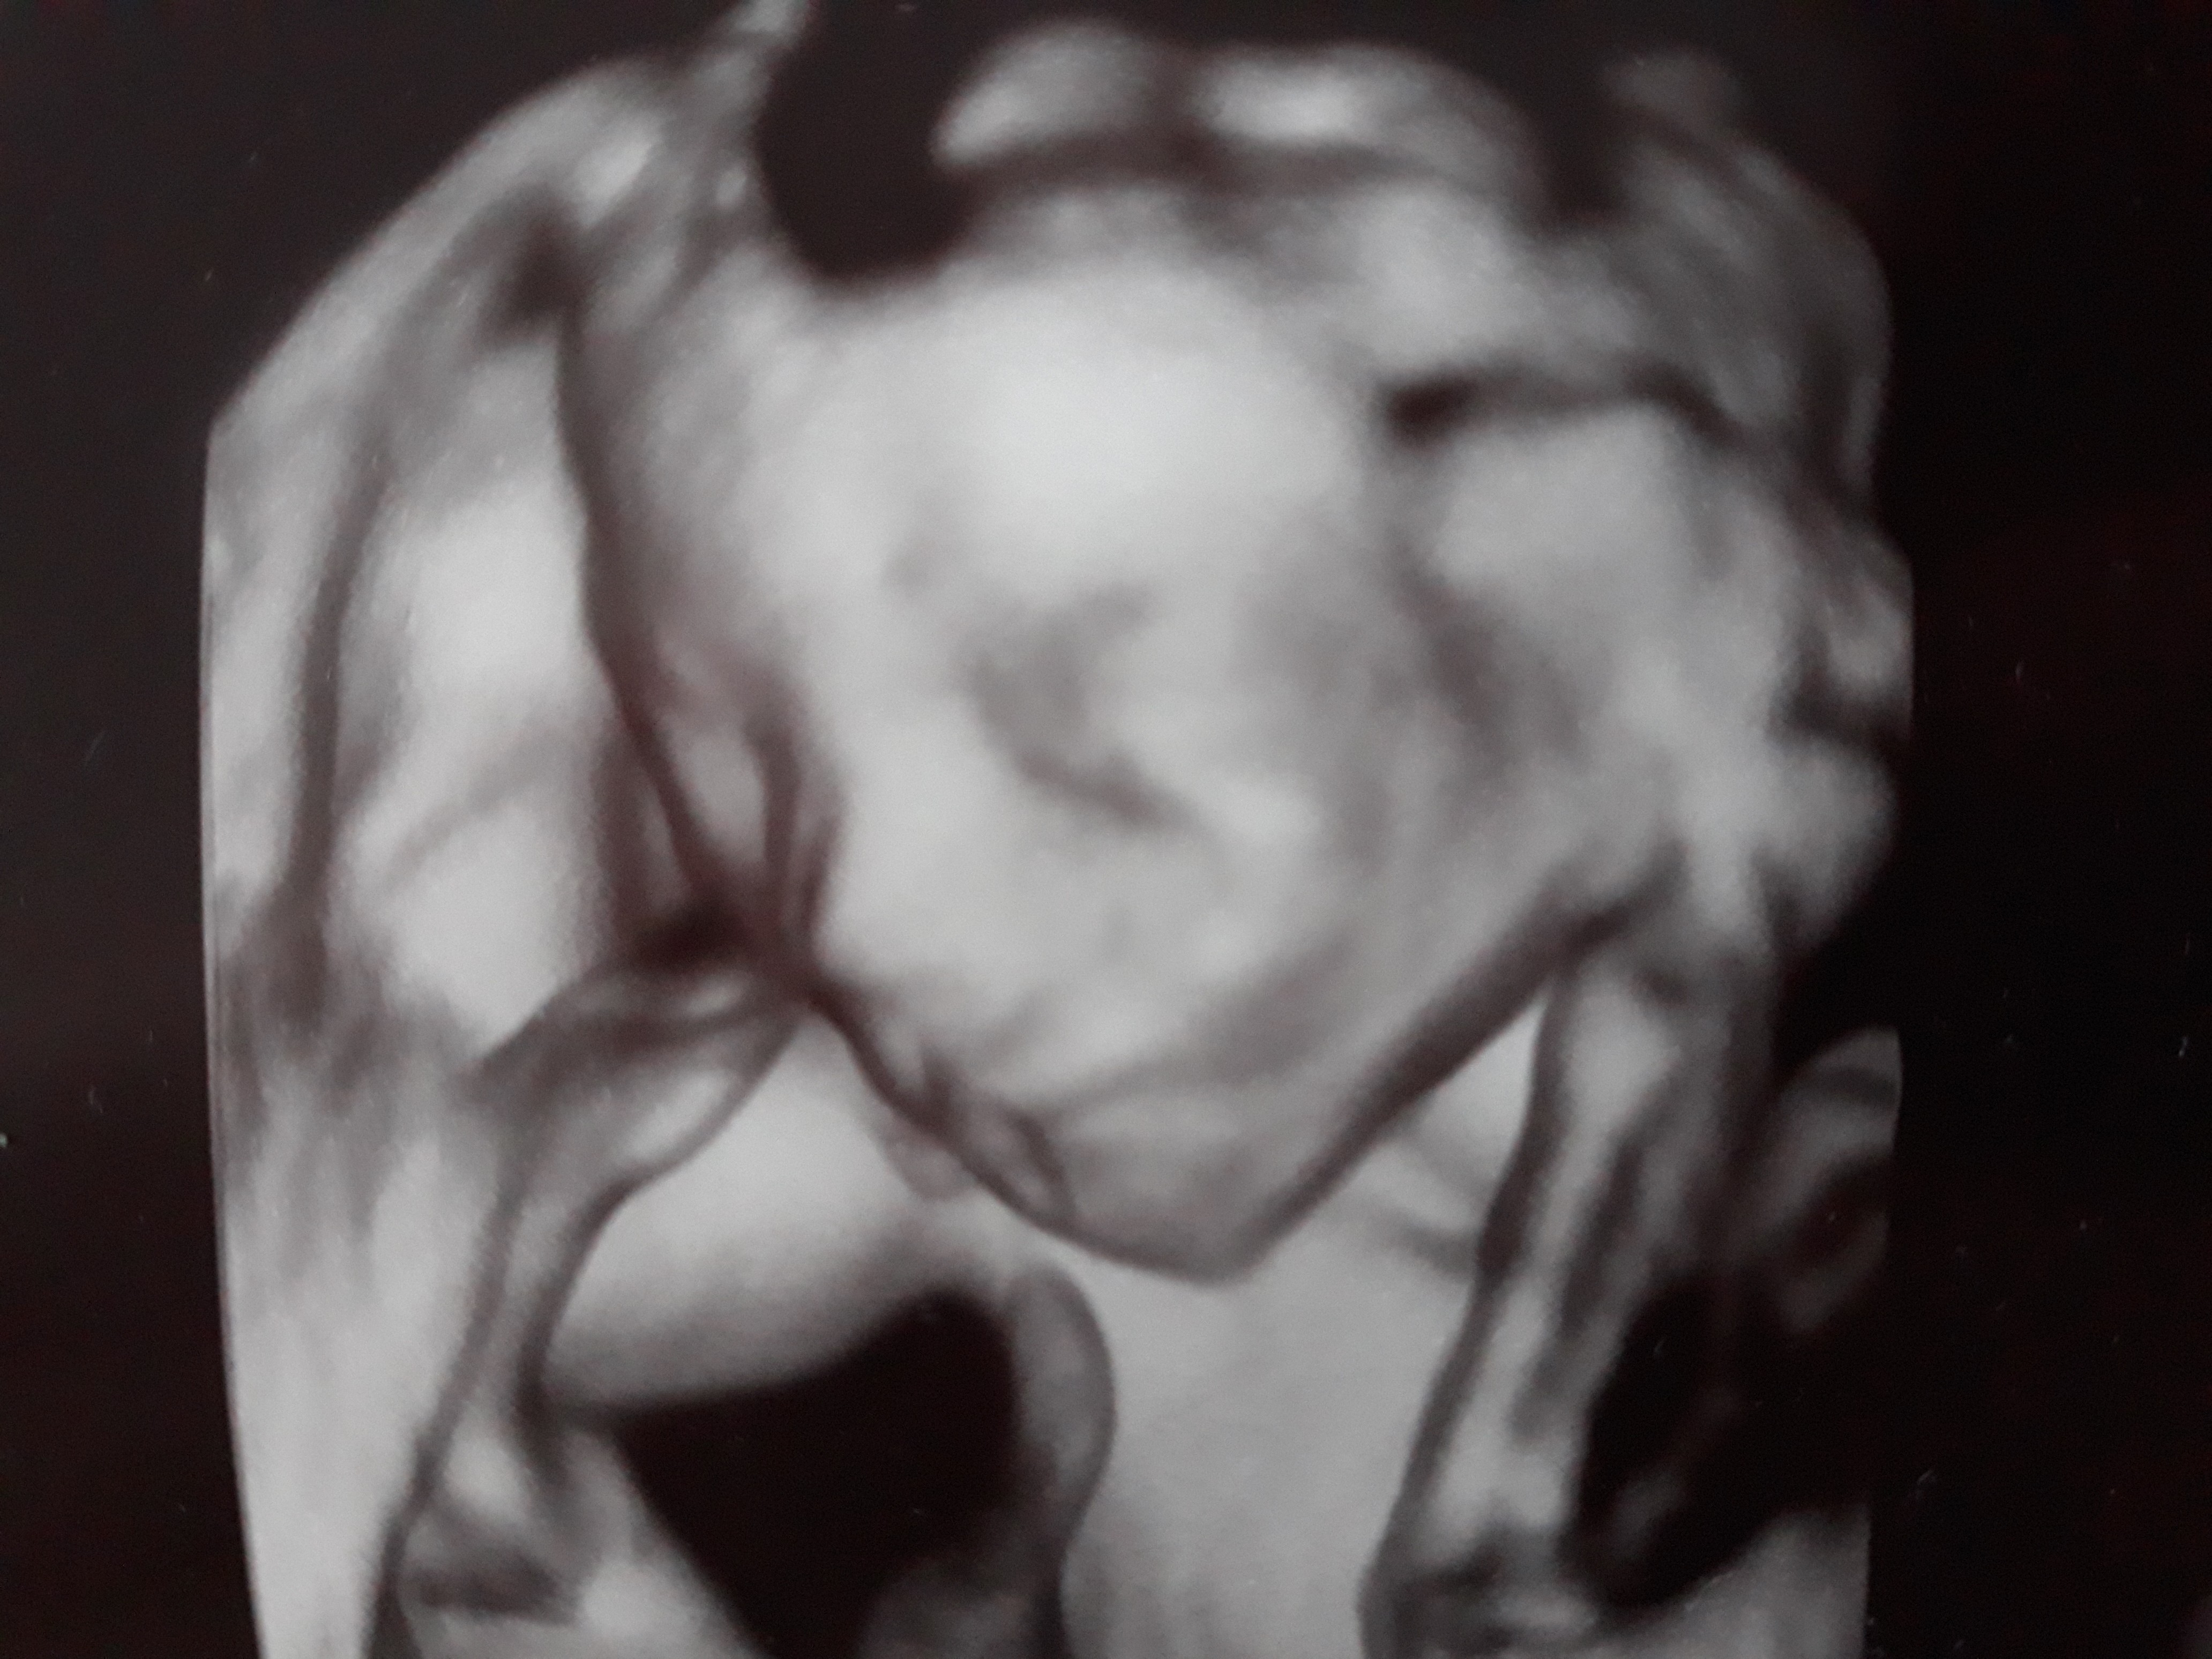

19+0 (wg usg i tego się teraz trzymamy!) wg OM 20+0

Waga : prawie 250 g i prawie 22 cm :biggrin2:

Tętno : 144(wczoraj), 150 (dzisiaj) :biggrin2:

Płeć : 100% chłopak :-) :)

Imię : Gabriel Mirosław :biggrin2:

Nosek - widoczny i śliczniutki (na prenatalnych podobno kośc nosowa była „nie do oceny”!)

Łożysko : na przedniej ścianie

Szyjka : 5 cm

Wszystkie narządy rozwijają się prawidłowo :-) :)

Termin porodu wg usg 20.04.2019 (jednak ze względu na cukrzycę typu2 nastąpi on 2 tygodnie wcześniej,ale konkretną datę poznam w późniejszym terminie) :-) :)